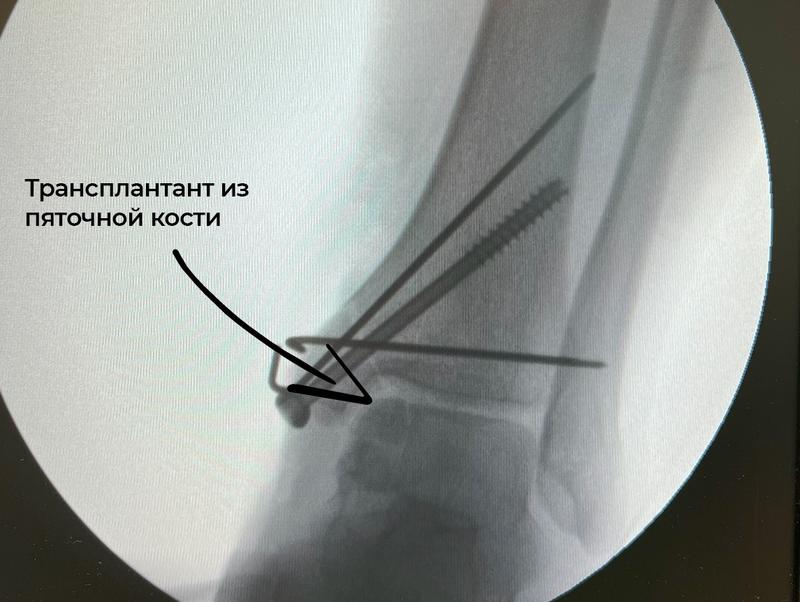

Василий Кузнецов доказал, что на пяточной кости в области прикрепления ахиллова сухожилия находится участок, где расположена хрящевая ткань - ее можно использовать в качестве трансплантата у подростка. Операцию впервые в Клиниках СамГМУ выполнили Андрей Шмельков и врач отделения Ольга Багдулина. Сейчас пациентке уже удалены металлофиксаторы, трансплантат прижился и девочка может ходить без боли и хромоты.